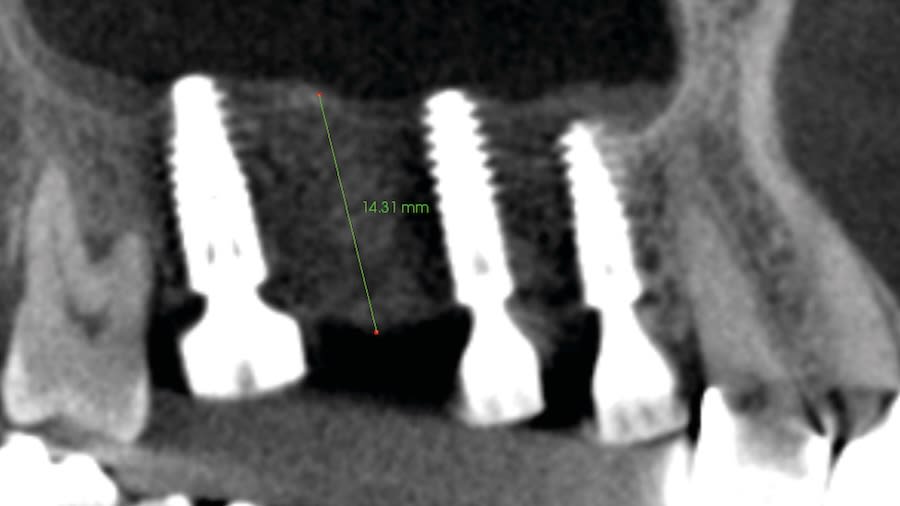

Step 4: Allow 4 to 6 months for the sinus graft healing. CBCT evaluation is needed to evaluate the available regenerated bone height for the implant placement. Reflect soft tissue utilizing standard surgical instruments, and use Densah burs for osseodensification site preparation to prepare the implant osteotomy and place the implant.

Case 1 (Figure 3 through Figure 24) depicts a 3-year follow-up of combined osseodensification sinus protocol IV in a severely resorbed maxillary ridge with ≤0.5 mm bone height in molar sites and horizontal deficiency at the first premolar site, using a two-stage approach for implant placement.